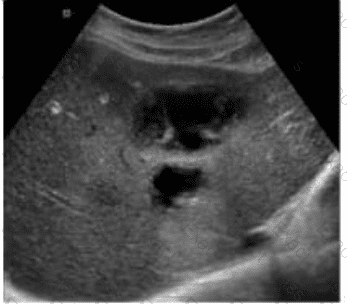

Which sonographic appearance of the bile ducts is demonstrated in this image?